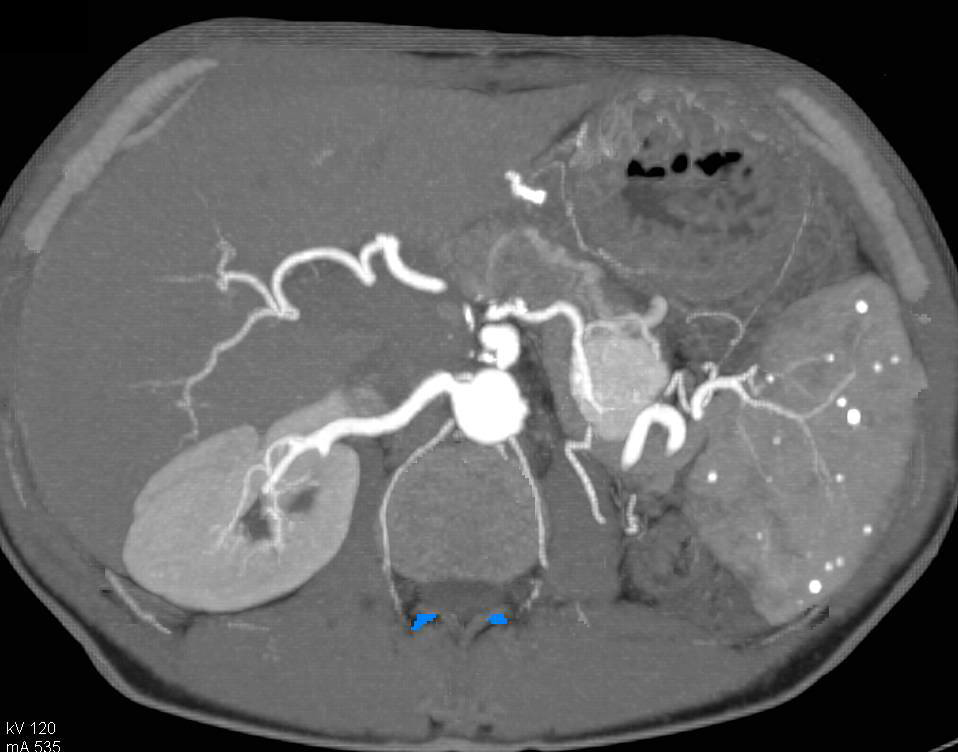

Recurrent Renal Cell Carcinoma Metastatic to the Pancreas